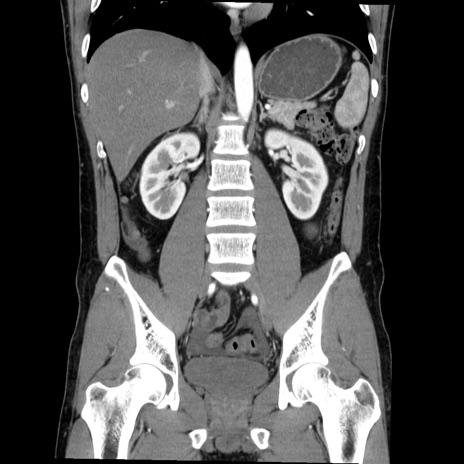

症例36(冠状断像)

【症例】20歳代 男性

【主訴】心窩部痛

【現病歴】今朝より上腹部痛あり。一旦軽快していたが再度出現したため救急要請。昨日夕に白身の魚を含む刺身を食べた。

【身体所見】BP 136/89mmHg、HR 74/min、BT 37.0℃、腹部:膨満、軟、心窩部に圧痛あり。反跳痛なし、筋性防御なし、腸雑音やや亢進あり。

【データ】WBC 17700、CRP 0.48